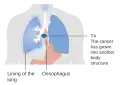

Staging

Staging is based on the TNM staging system, which classifies the amount of tumor invasion (T), involvement of lymph nodes (N), and distant metastasis (M).[17] The currently preferred classification is the 2010 AJCC staging system for cancer of the esophagus and the esophagogastric junction.[17] To help guide clinical decision making, this system also incorporates information on cell type (ESCC, EAC, etc.), grade (degree of differentiation – an indication of the biological aggressiveness of the cancer cells), and tumor location (upper, middle, lower, or junctional[50]).[51]

-

T1, T2, and T3 stages of esophageal cancer -

Stage T4 esophageal cancer -

Esophageal cancer with spread to lymph nodes